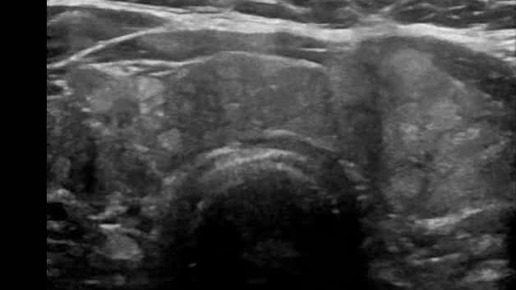

Видео к статье "Стратификация узлов щитовидной железы. TI-RADS-3" https://dzen.ru/a/Zv4svErHVi-eImKZ

Ультразвуковые находки от врача УЗД Зорина Я.П.